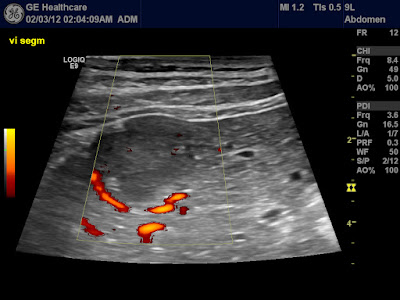

| Perilesional hypervascularity |